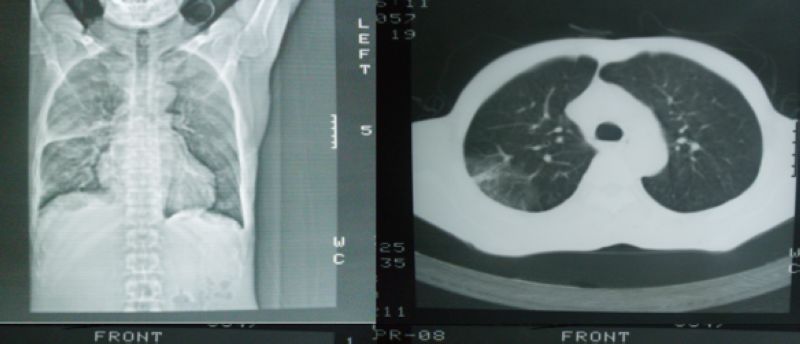

以下是引用hyhxn在2008-4-16 18:10:00的发言:[br]右中下肺炎症感染,没有纵隔窗?